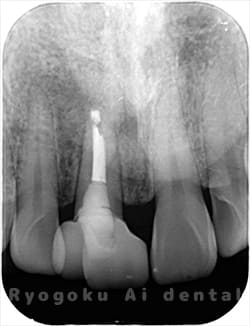

Case10

-

- 原因

- 下顎前歯部歯根嚢胞

- 治療内容

- 歯根端切除法

- 治療費用

- ¥77,000×2

他院で歯根端切除術を行ったが、良くならないとのことで、ご来院された患者様です。再根管治療後、サイナストラクトが消失しなかったため、歯根端切除術を行いました。現在、一年経過しておりますが、再発もせず、経過良好です。